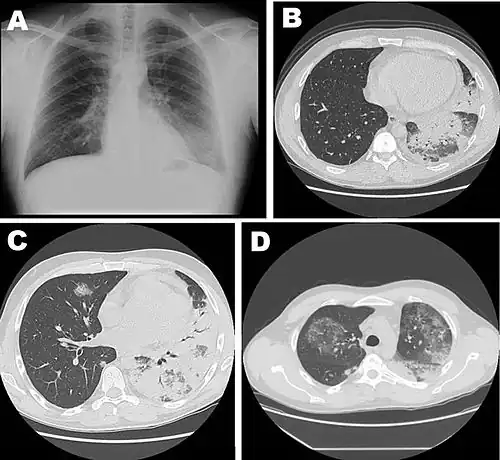

Various stages of the disease: Chest radiograph (A) and high-resolution computed tomography (B) at hospital admission, repeat high-resolution computerized tomography of the chest a week after hospital admission (C, D), shown in a 42-year-old male with severe pneumonia caused by L. pneumophila serogroup 11a